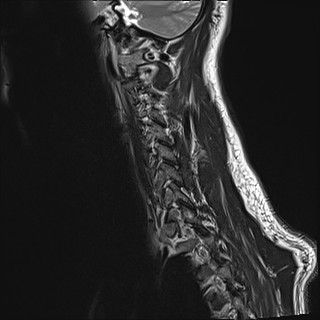

Wirbelsäule HWS

t1_tse_sag